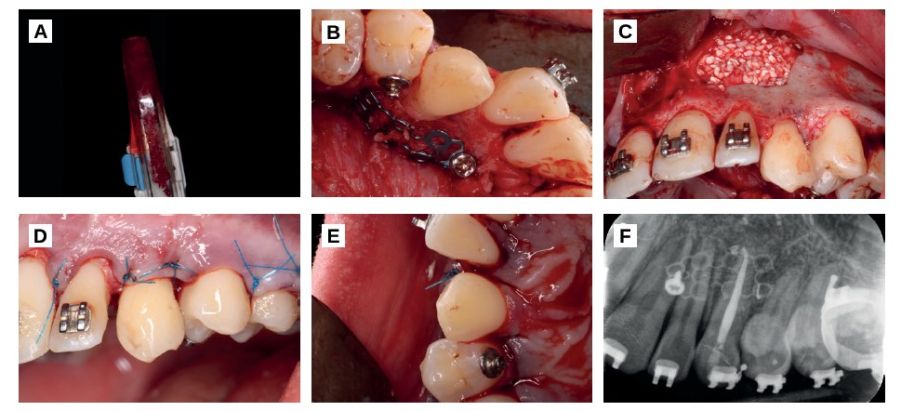

For palatal regeneration, local supraperiosteal infiltrative anaesthesia was placed in the bottom of the lower molars of the 4th quadrant and an intrasulcular incision was made in the first and second right lower molar (4.6 and 4.7) that was continued with a linear incision through the mandibular ramus. The total thickness of the vestibular flap was detached and autologous particulate bone of the mandibular ramus was obtained with a bone scraper (Figure 3). Once enough autologous bone was obtained, the retromolar gap was stitched with 5/0 monofilament suture with simple stitches.

In the palatine a titanium mesh was placed fixed with two osteosynthesis screws (Stryker, Michigan, USA).

The created space was filled with particulate autologous bone mesh in order to regenerate the area of the tooth that was outside the bone (Figure 3) and the vestibular was regenerated with biomaterial (Apatos, Osteógenos, Madrid, Spain), since it was a self-contained cavity (Figure 3).

Finally, the flap was sutured with simple stitches repositioning the papillae, with a monofilament suture 5/0. The occlusion was reduced until it did not make contact with any other tooth and the canine was ferulized with the orthodontic arch itself (Figures 3 and 3) for 2 weeks.

After 2 weeks of the surgery, periapical X-rays were taken and a root canal of the canine was performed under absolute isolation (Figure 3).